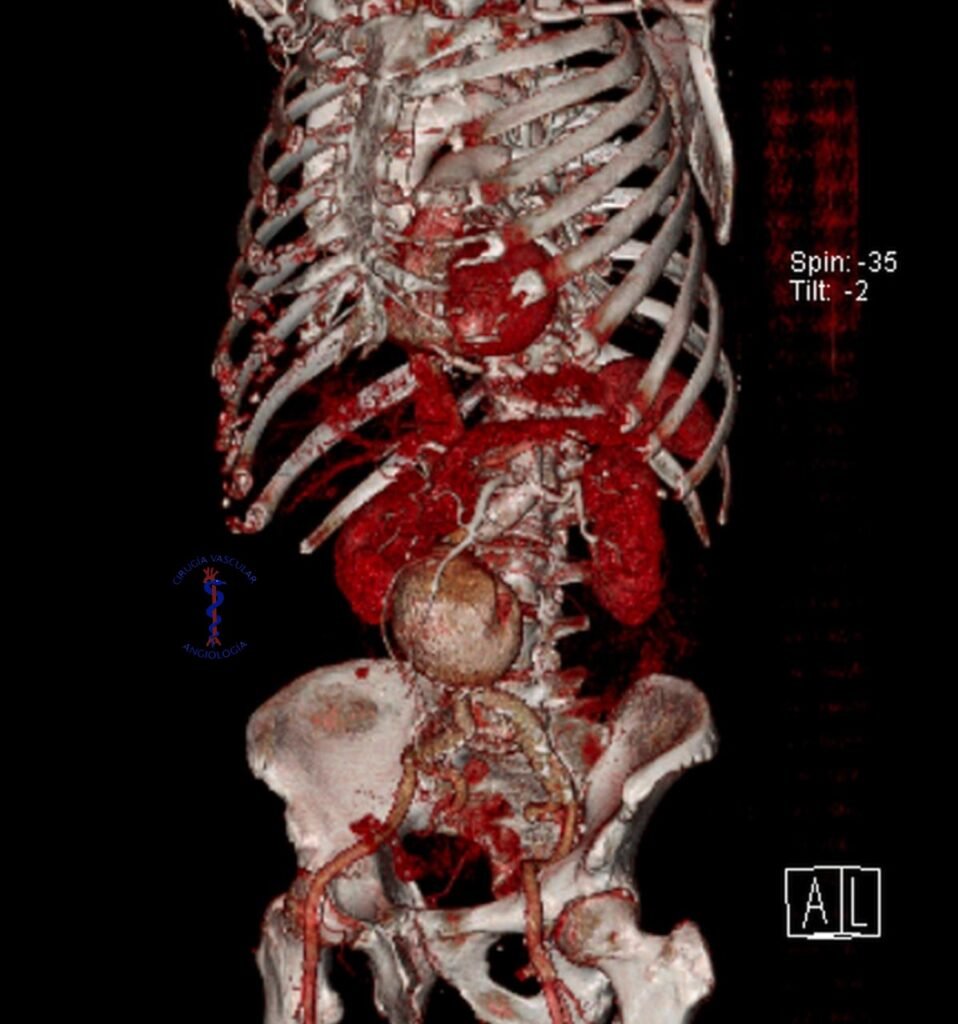

Aneurisma de aorta abdominal

Es la dilatación de las arterias del abdomen, en ocasiones pueden presentarse como un dolor abdominal severo, son de alto riesgo ya que la arteria puede romperse y ocasiones defunción por sangrado masivo, se realiza la cirugia de dos formas, abierta: donde se coloca una arteria artificial llamada injerto o por cateterismo: donde se coloca una endoprotesis que es un tipo de injerto especial.